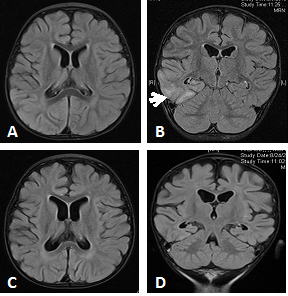

The EEG at 14 months of age showed a diffuse slowing of background activity with multifocal paroxysmal activity with sharps, spikes and slow wave activity predominately seen at the central, parietal region and posterior quadrant of the right hemisphere, consistent with multifocal seizures. Repeated brain MR imaging was remarkable for right temporal lobe hyperintensity on T2/FLAIR with no diffusion restriction or abnormal enhancement. Mild atrophic changes were more obvious at the right cerebral hemisphere. Another brain MRI 4 months later showed interval regression of the previously noted abnormalities and diffuse cerebral atrophy (Figure 1). The possibility of mitochondrial disease was entertained based on the clinical picture and positive family history of similar case, and further molecular rapid gene analysis revealed the presence of a previously reported homozygous mutation c.3286C>T (p.Arg1096Cys) in exon 21 of POLOG, thus confirming diagnosis of POLG- related hepato-cerebral form of mtDNA depletion syndrome, AHS.

Figure 1 Brain MRI at 14-months of age with postictal changes seen in epilepsia partialis continua with AHS (A) axial, and (B) coronal T2W/ Fluid-attenuated inversion recovery (FLAIR) sequences showing: a focal high-signal-intensity lesion in the right temporal lobe (predominantly lower and lateral portion) with no diffusion restriction or abnormal enhancement. Mild atrophic changes seen in the right cerebral hemisphere with prominent right lateral ventricle.

Follow-up study at 16-months of age (C) axial, (D) coronal T2W/ Fluid-attenuated inversion recovery (FLAIR) sequences showing: interval regression of the previously noted hyperintensity in the right temporal lobe with no signs of atrophy or enhancement. Same previous mild right cerebral atrophy. Slight enlargement of the size of lateral and third ventricle with no signs of active e hydrocephalus.

Cranial CT and MRI scans usually demonstrate generalized atrophy of both the cortex, and white matter at the end stage of the disease. Characteristic hyperintensities signaling abnormalities on T2/ FLAR MRI sequences involving metabolically active occipital and sensorimotor cortical regions can be detected. Lesions of the thalamus have also been reported.13,18 In this report, brain MRI revealed global brain atrophy in both siblings, while changes in the temporal lobe abnormality that resolved with time on neuroimaging have been reported previously in AHS and may be attributed to prolonged seizure activity.